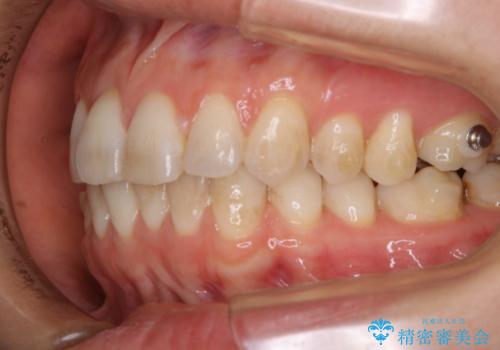

- インビザライン矯正治療中にステインが気になるとのことで来院されました。全体的にステインが付着していたため自費クリーニングPMTC(60分コース)を行いました。

インビザライン矯正治療中は、ご自身の歯にアタッチメントという突起物(効率的に歯の移動を行うため)をつけます。そのため、通常時よりもステインが付きやすい状態になることがあります。

インビザラインは透明なマウスピースなので、ご自身の歯にステインなどが付着していると、見た目に影響してしまうことがあります。